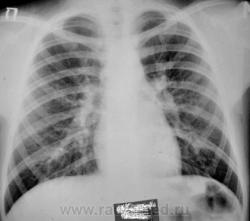

Девочка 10 лет. В течении трех недель беспокоит кашель, насморк, температуры не было, контакт с ОРВИ по дому. На 7.09.10 в легких выслушиваются разнокалиберные хрипы по всем полям,кашель, насморк. За весь период болезни получила симптоматическую терапию (климбутерол, виброцил, зиртек, эреспал, грудной сбор, физиотерапия). В ОАМ и ОАК без изменений.

Спасибо за улучшение качества снимков! Все может быть. Но уж больно смущают корни, особенно в боковой проекции

Мне тоже кажется, что корни расширены. Бронхоаденит тут не исключить. Требует дальнейшего обследования, оптимально - КТ груди с внутривенным контрастированием, для лучшей визуализации структур средостения. При отсутствии возможности - линейные томограммы.

Да, и томография нужна, да, и консультация фтизиатра не лишней будет.